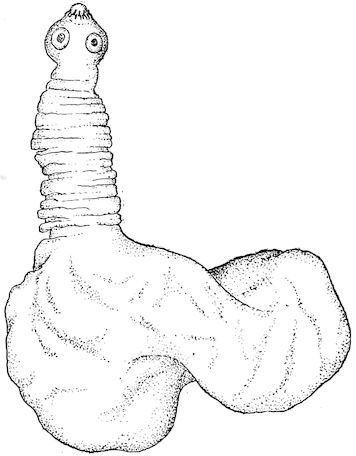

Fig. 5.—Head of a pig suffering from osseous cachexia.

Fig. 7.—Osseous cachexia: softening of the maxillæ.

Fig. 8.—Transverse section through the middle region of the face in a pig suffering from osseous cachexia.

18In the final stages, the bones may be cut with a knife, and a time arrives when bony tissue seems completely to have disappeared; thus, as shown in Fig. 8 herewith, it was possible to cut the entire head of a pig into thin slices without the slightest difficulty. All parts of the head had been affected by the softening change.